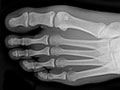

An extremity X-ray is a picture of your hand, wrist, arm, foot, ankle, knee, hip, or leg. It is done to see whether a bone has been fractured or a joint dislocated. It is also used to check for an injury or damage from conditions such as an infection, arthritis, bone growths (tumors), or other bone diseases, such as osteoporosis.

An extremity X-ray is a picture of your hand, wrist, arm, foot, ankle, knee, or leg. It is done to see whether your bone has been fractured or your joint dislocated. It is also used to check for an injury or damage from conditions such as infection, arthritis, bone growths (tumors), or other bone diseases, such as osteoporosis. In an emergency, the doctor can see the initial results of an extremity X-ray in a few minutes. Otherwise, a radiologist usually has the official X-ray report ready the next day.